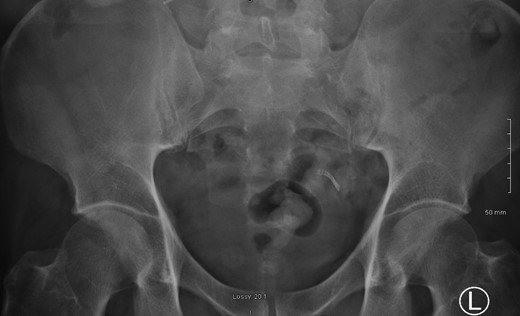

A 52-year male was referred to the surgical team for a 1-day history of left iliac fossa pain accompanied by nausea and the inability to open his bowels for 48 hours. The pain was 9/10 in severity, sharp, persistent and with a gradual worsening onset. The patient was previously diagnosed with extensive diverticular disease and admitted 2 months prior with acute sigmoid diverticulitis. 18 months earlier he underwent an emergent laparoscopy for an unclear pelvic inflammatory mass on CT, that suggested either severe sigmoid diverticulitis or appendicitis. He also had multiple polyps throughout the colon, that were endoscopically removed. The patients past medical history was significant for a non-flow limiting coronary artery disease, arterial hypertension and an allergy to penicillin and tetracycline. Temperature on admission was 38.7 C, blood pressure of 149/109 mm/Hg, pulse of 109 bpm and a respiratory rate of 20/min with O2-saturations of 96% on room air. The abdomen was soft with tenderness and guarding over the left iliac fossa. Bowel sounds were present. Investigations showed a white cell count of 17.6 tsd/ul and a CRP of 64 mg/l. No pneumoperitoneum was detected on an erect chest x-ray. Treatment with ciprofloxacin and metronidazole was started and the patient kept nil per mouth. CT imaging showed extensive sigmoid diverticular disease with marked pericolonic fat stranding and free gas tracking into the mesenteric fat. Gentamycin was added and within 3 days the patient’s clinical symptoms improved. He was apyrexic and the white cell count dropped to 10.9 tsd/ul. A repeat CT scan showed a stable appearing localized perforation with reduced free gas and no signs of collection. However, of note was a small curvilinear metallic foreign body within the lumen of the sigmoid colon of uncertain etiology (Fig. 1). On questioning, the patient recalled a mechanical fall with a head contusion 9 days prior to admission during which he lost his partial denture. The patient was commenced on laxatives and despite bowel movement on the following day, the foreign body did not pass. A PFA showed the persistent presence of the metallic foreign body over the sigmoid colon, which raised the suspicion of impaction (Fig. 2). The patient was prepared for colonoscopy and the foreign body was identified impacting the lumen of the sigmoid colon (Fig. 3). However, endoscopic retrieval failed and the decision was made to proceed with laparoscopic anterior resection. Intraoperative findings showed a rigid and thickened sigmoid colon with adhesions and a diverticular abscess. About 22 cm of sigmoid colon was resected and the procedure was completed with a primary colo-rectal end to end anastomosis, using a 31 mm CEEA-Stapler. The resected sigmoid colon contained the lost partial denture, which showed impaction and perforation into the sigmoid mesocolon (Fig. 4). Following surgery, the patient was transferred to the surgical ICU for 24 h observation and discharged home after one week.

Colonoscopy identified a non-retrievable foreign body impacting the lumen of the sigmoid colon.